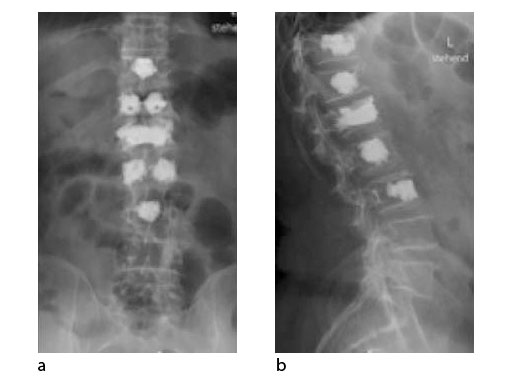

A 78-year-old woman was affected by steroid induced osteoporosis. She had persisting pain (mechanic and muscular) due to static imbalance (hyperkyphosis) and nonunion 8 months after a minor trauma with a vertebral compression fracture and vertebra plana of L1, and development of symptomatic stenosis of the spinal canal with loss of mobility over time. Pre-existing degenerative lumbar scoliosis was increased by the fracture.

A 76-year-old man was affected by advanced osteoporosis (SD -2.5) (alcohol, steroids).